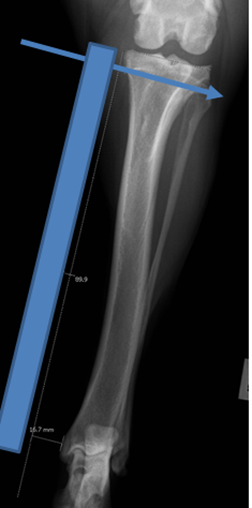

Radiographic Planning: Positioning